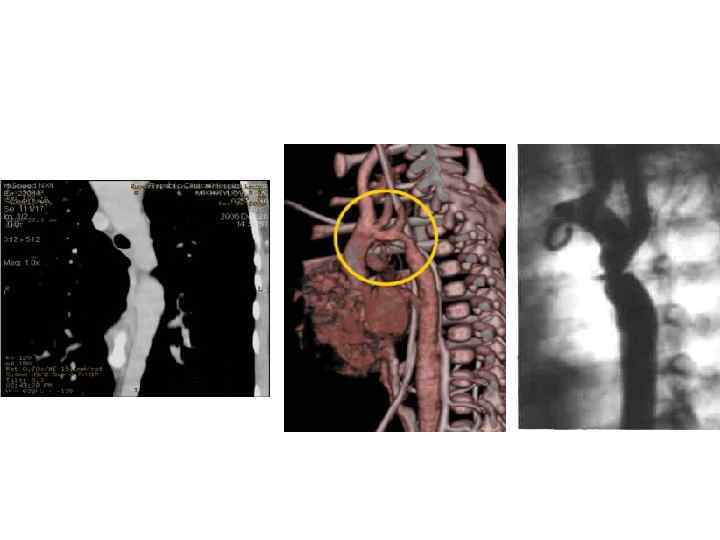

КОАРКТАЦИЯ АОРТЫ 1. В ОСНОВНОМ ГОЛОВНАЯ БОЛЬ ПЕДИАТРОВ 2. ТЕРАПЕВТЫ ВИДЯТ ОПЕРАТИВНО КОРРЕКТИРОВАННЫХ БОЛЬНЫХ 3. АГ ЛЕЧИТСЯ КАК ГБ, НО НАДО ПОМНИТЬ О ЧАСТОМ АТЕРОСКЛЕРОЗЕ (СИСТОЛИЧЕСКАЯ АГ) И ГИПОПЛАЗИИ ПОЧЕК (НЕФРОГЕННАЯ АГ)

КОАРКТАЦИЯ АОРТЫ 1. В ОСНОВНОМ ГОЛОВНАЯ БОЛЬ ПЕДИАТРОВ 2. ТЕРАПЕВТЫ ВИДЯТ ОПЕРАТИВНО КОРРЕКТИРОВАННЫХ БОЛЬНЫХ 3. АГ ЛЕЧИТСЯ КАК ГБ, НО НАДО ПОМНИТЬ О ЧАСТОМ АТЕРОСКЛЕРОЗЕ (СИСТОЛИЧЕСКАЯ АГ) И ГИПОПЛАЗИИ ПОЧЕК (НЕФРОГЕННАЯ АГ)